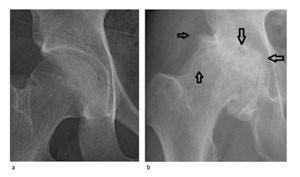

Diagnosen artrose stilles ved anamnese, klinisk undersøkelse og røntgenundersøkelse. Typiske funn på røntgenbilder er osteofytter, cyster og subkondral sklerose (fig 2). Den viktigste artroseindikatoren på vanlige røntgenbilder er avsmalning av leddspalten (7). På røntgenbilder kan man avdekke andre patologiske tilstander, f.eks. tumor og infeksjon. Dersom f.eks. rubor, hevelse eller allmennsymptomer gir mistanke om leddgikt eller krystallartritt, undersøkes leddvæsken med tanke på krystaller, og i serum måles inflammasjonsmarkører og revmatisk faktor. Røntgenundersøkelse er nødvendig for å bekrefte diagnosen artrose, men graden av røntgenforandringer sier lite om hvor mye plager pasienten har (8).